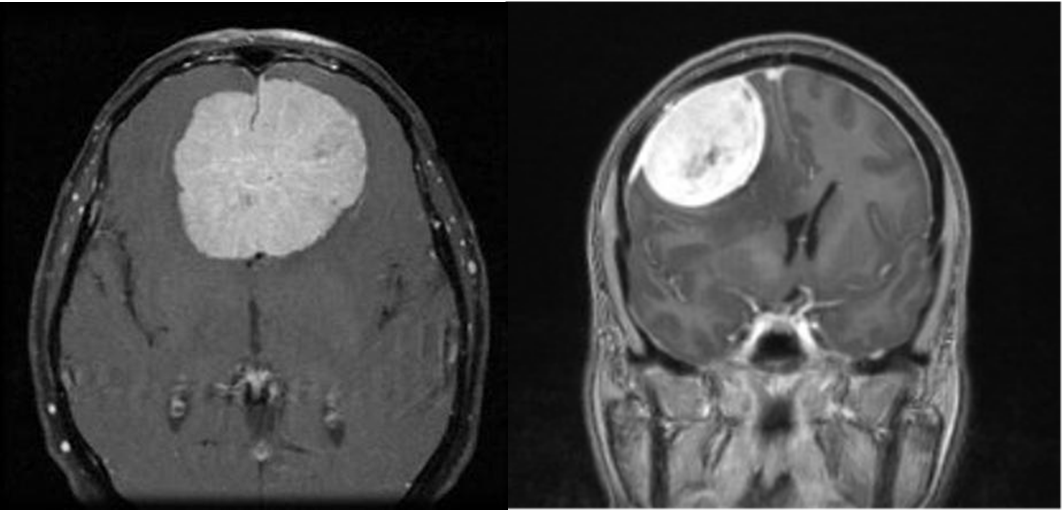

- Meningiomas: el tumor cerebral primario más frecuente que se desarrolla a partir de las meninges, las membranas que cubren al cerebro y la médula espinal.

Más allá de las señales de alerta mencionadas, cada persona puede presentar síntomas diferentes y a la vez, la presencia de uno o varios de ellos no necesariamente indica la existencia de un tumor cerebral. Cuando un paciente llega con un cuadro sospechoso, el primer estudio de urgencia que se suele realizar es una tomografía de cerebro aunque el doctor Chaves nos aclaró que este estudio no es suficiente.

“El estudio ideal para descartar un tumor es una resonancia magnética de cerebro con y sin contraste. Y el diagnóstico final y definitivo se da por el estudio del tejido tumoral por un médico anátomo-patólogo. Esto se puede lograr tomando una pequeña muestra a través de una biopsia o con el análisis del tejido obtenido luego de una resección quirúrgica”, detalló.

Una vez confirmado el diagnóstico de un tumor cerebral, el tratamiento puede incluir la cirugía para extirparlo. “Se emplean intervenciones específicas, como son la neurocirugía con técnica microquirúrgica, la asistencia con neuronavegación, la radioterapia, que incluye una forma específica que se llama radiocirugía estereotáxica para destruir la células cancerosas y la quimioterapia para inhibir el crecimiento tumoral. El plan de tratamiento dependerá de las características particulares de cada paciente”, agregó. En algunos casos los tumores cerebrales pueden regresar después de la terapia inicial. La recurrencia puede demandar un nuevo enfoque de tratamiento con cirugía adicional, radioterapia o quimioterapia.